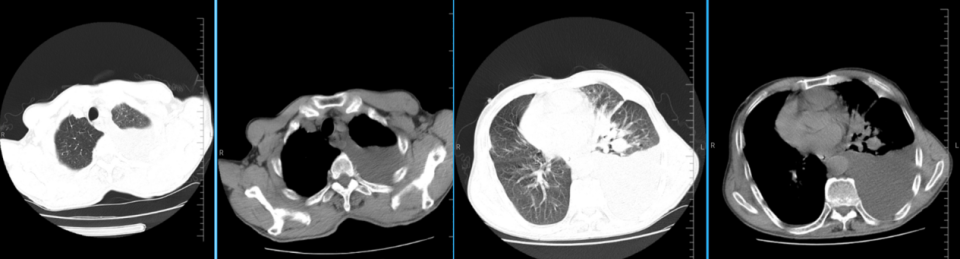

患者20余天前出现呼吸困难,活动后明显,有咳嗽、咳白痰。2025年7月30日,当地医院肺部CT提示“左肺感染伴左侧胸腔积液”,遂住院,行胸水引流,为淡黄色清亮液体。2025年8月1日胸水化验:总蛋白12.2g/L,LDH93U/L,单个核细胞93%,多个核细胞 7%,李凡他试验阴性,且胸水病理未找到肿瘤细胞。外院予左氧氟沙星抗感染治疗,治疗后复查胸部CT左肺感染及胸腔积液基本吸收(胸水引流前后CT见图1a、图1b),后出院。

出院后,患者短期内再次出现咳嗽加重,胸闷加重,无发热等其他不适。2025年8月13日就诊我院急诊,肺部CT提示左侧大量胸腔积液,血氧饱和度下降,急诊予以胸腔穿刺(胸水引流前CT见图2)。仍旧是淡黄色清亮液体,胸水常规提示:有核细胞:289*10^6/L,嗜酸性粒细胞2%,吞噬细胞1%,间皮细胞:3%,中性粒细胞11%,淋巴细胞75%,巨噬细胞8%。胸水生化:总蛋白10.0g/L,腺苷脱氨酶2U/L,乳酸脱氢酶53U/L。后患者收入我科。

图1a:2025.07.30外院胸腔积液穿刺前CT

图1b:2025.08.06外院胸腔积液穿刺后CT

图22025.08.13我院急诊CT:左肺散在炎症,左侧胸腔大量积液伴左肺大部不张实变